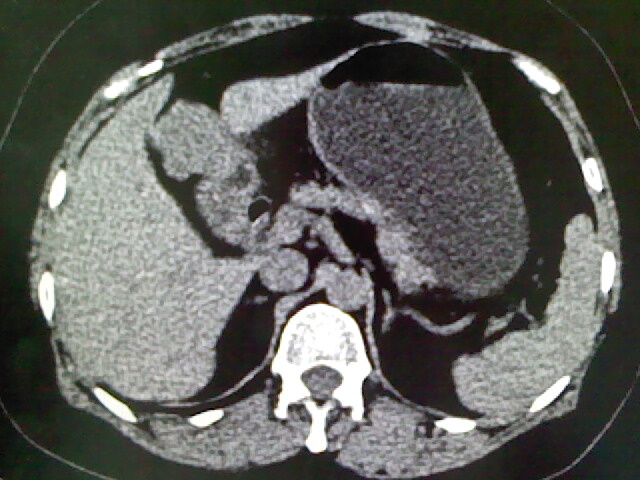

以下是引用卜一在2009-4-2 13:26:00的发言:[br]胆囊颈部结石伴胆囊炎!另:建议增强,待除外肝内占位及胆囊占位!

以下是引用liaoqiang在2009-4-2 16:23:00的发言:[br]胆囊是否切除?胆囊颈区致密影考虑金属夹?结石?肝脏右叶低密度影,考虑增强。